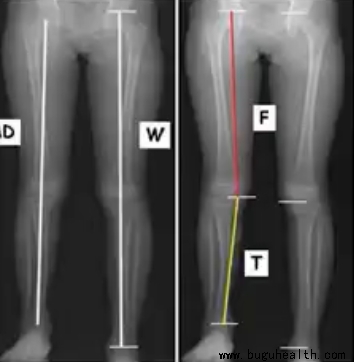

X射线——仰卧位

X射线相对准确可靠,可以显示人体代偿下肢不等长情况。但是它也存在辐射,不能提供股骨及胫骨具体的测量,同样也较昂贵、耗时,并非随时可用。